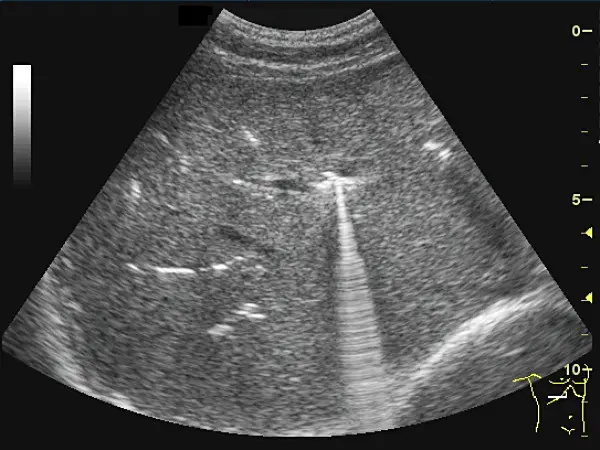

肝臟超音波掃描時,發現多處呈現散在性的明亮高回音性線狀物,部分區域出現音波迴盪(reverberation)現象如下圖所示,最有可能的診斷為何?

- 肝臟超音波背景:影像顯示肝臟實質構造。

- 高回音病灶:在肝臟實質內(偏中央與沿著膽管分布處),可觀察到多處散在性、極度明亮(強烈高回音,hyperechoic)的線狀或點狀結構。

- 特徵性假影:從這些高回音結構的後方,可以明顯看到一道道垂直向下延伸、如掃把或梳子般的連續亮帶。這在超音波學上稱為音波迴盪假影(Reverberation artifact)或更精確地稱為振鈴假影(Ring-down artifact)。 綜合以上特徵,這是「肝內氣體」在超音波下最經典的影像表現。

- (A) 膽道氣腫(pneumobilia):正確。膽道內積氣時,氣體會產生極強的反射,呈現高回音的線狀物(勾勒出膽管的形狀)。同時,超音波在氣泡間反覆震盪,會產生明顯的「音波迴盪(reverberation)現象」或「振鈴假影(ring-down art